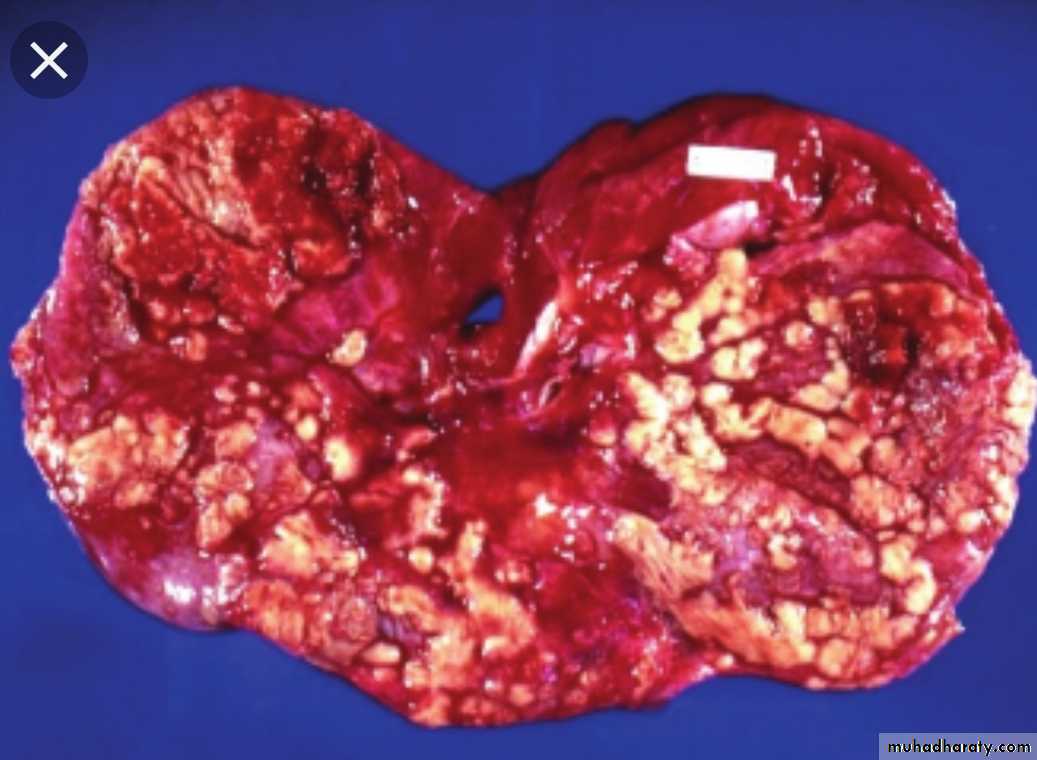

Actinomycosis

Caused by Actinomyces israelliiVirtually anaerobic, gram-positive, long filamentous bacteria.

Closely related to mycobacteria with some similarity to fungi.It can be found as a commensal m.o. in the mouth , G.I.T., female genital tract. Only occasionally they invade the tissues it produce infection.

1- Cervicofacial lesion (70%).

2- Abdomial lesion (around iliocecal region or appendix) (15% ).3- Pulmonary lesion (10%).

4- Subcutaneous lesion (5%).

5- Gynecological infection in female with IUCD.

Pathology

Infection produces firm masses containing numerous abscesses ( honeycomb abscesses) bearing colonies as yellowish granules (sulfur granules) with sinuses & fistulae.